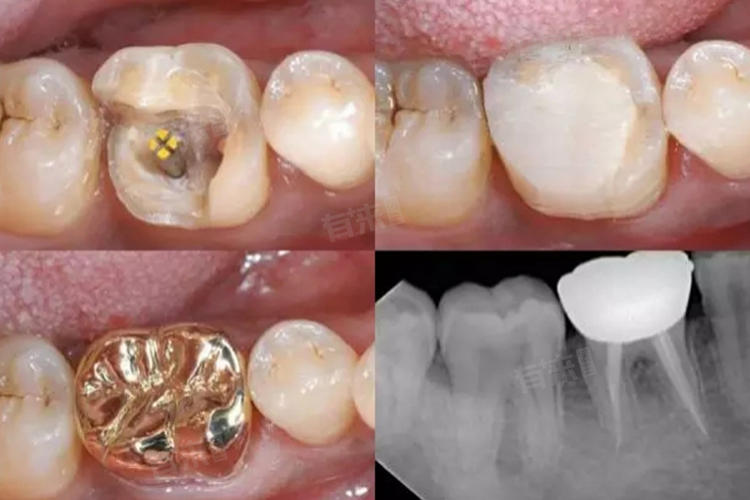

- 烤瓷熔附金属全冠:兼具金属的强度和瓷的美观,颜色、外观逼真,与自身的牙齿相比难以察觉。色泽稳定,表面光滑,耐磨。

- 桩核冠:由桩、核和全冠组成,利用固定桩插入根管内而获得固定的一种全冠修复体。

- 金属牙套:通常由合金制成,包括镍合金、钴铬合金、金合金等,强度高、耐用,但可能影响磁共振成像。